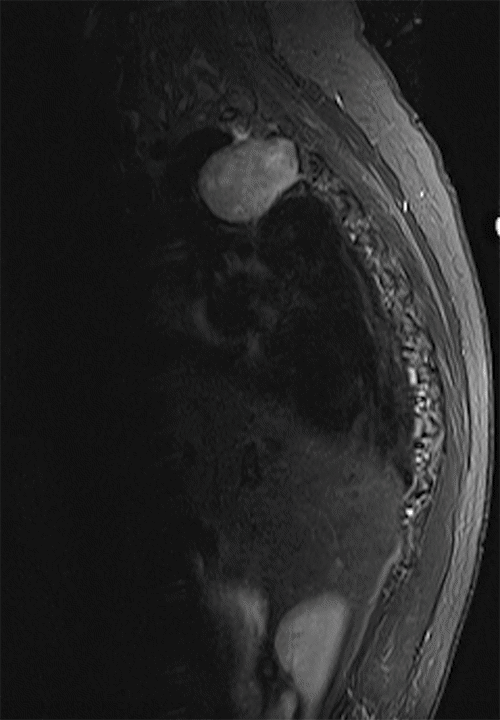

Figure 2. Repeat MRI in Routine Office Follow-Up: Sagittal FLAIR Sequence. Published with Permission

A. The mass essentially unchanged in size from the prior study, about five years prior.

The patient was followed for 30 years without progression and had a repeat MRI, which showed stability of the mass (Figure 2). Over a few months, the patient noticed difficulty walking and numbness in the torso and lower extremities. She was re-evaluated in the office, where her neurologic constellation of symptoms included vague decreased sensation below the level of T4, unsteady balance, and abnormal plantar (Babinski) reflex. No focal motor deficits were present in the lower extremities. A repeat MRI was then obtained at the time of showing an increase in the size of the mass compared to before (Figure 2), with growth inwards, causing a significant mass effect on the spinal canal and moderate to severe compression of the spinal cord. It also caused severe right neural foraminal narrowing at the level of T2–T3, resulting in nerve-root impingement (Figure 2).